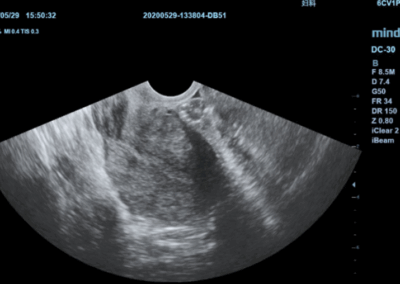

Los sistemas ecográficos estándares disponibles en la actualidad generalmente permiten un diagnóstico básico, pero carecen de funcionalidades avanzadas. Ahora, el DC-30 FullHD es la respuesta perfecta para un rendimiento de imagen de alta calidad, con una pantalla táctil de 21,5 pulgadas y funciones avanzadas como Auto IMT, iScape, elastografía Natural Touch, imágenes con contraste UWN e imágenes Doppler tisulares en el ámbito de las imágenes generales, y Smart OB, Smart face e iLive en el ámbito de la obstetricia.